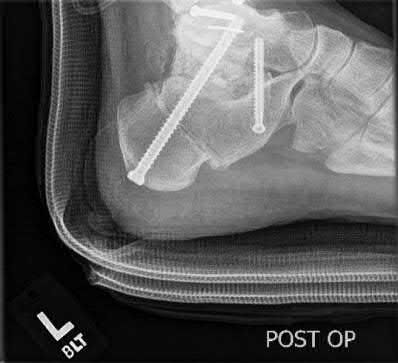

Question 9:

A 30-year-old male sustains a severe midfoot sprain. Radiographs reveal widening between the bases of the first and second metatarsals. The primary ligamentous stabilizer disrupted in this classic Lisfranc injury connects which two osseous structures?

Correct Answer: Medial cuneiform to 2nd metatarsal base

Explanation:

The Lisfranc ligament is the strongest ligament in the tarsometatarsal joint complex. It courses obliquely from the lateral aspect of the medial cuneiform to the medial base of the second metatarsal. It acts as the primary stabilizer of the second metatarsal base. Disruption results in the classic widening between the first and second rays, often with an avulsion fragment ('fleck sign').